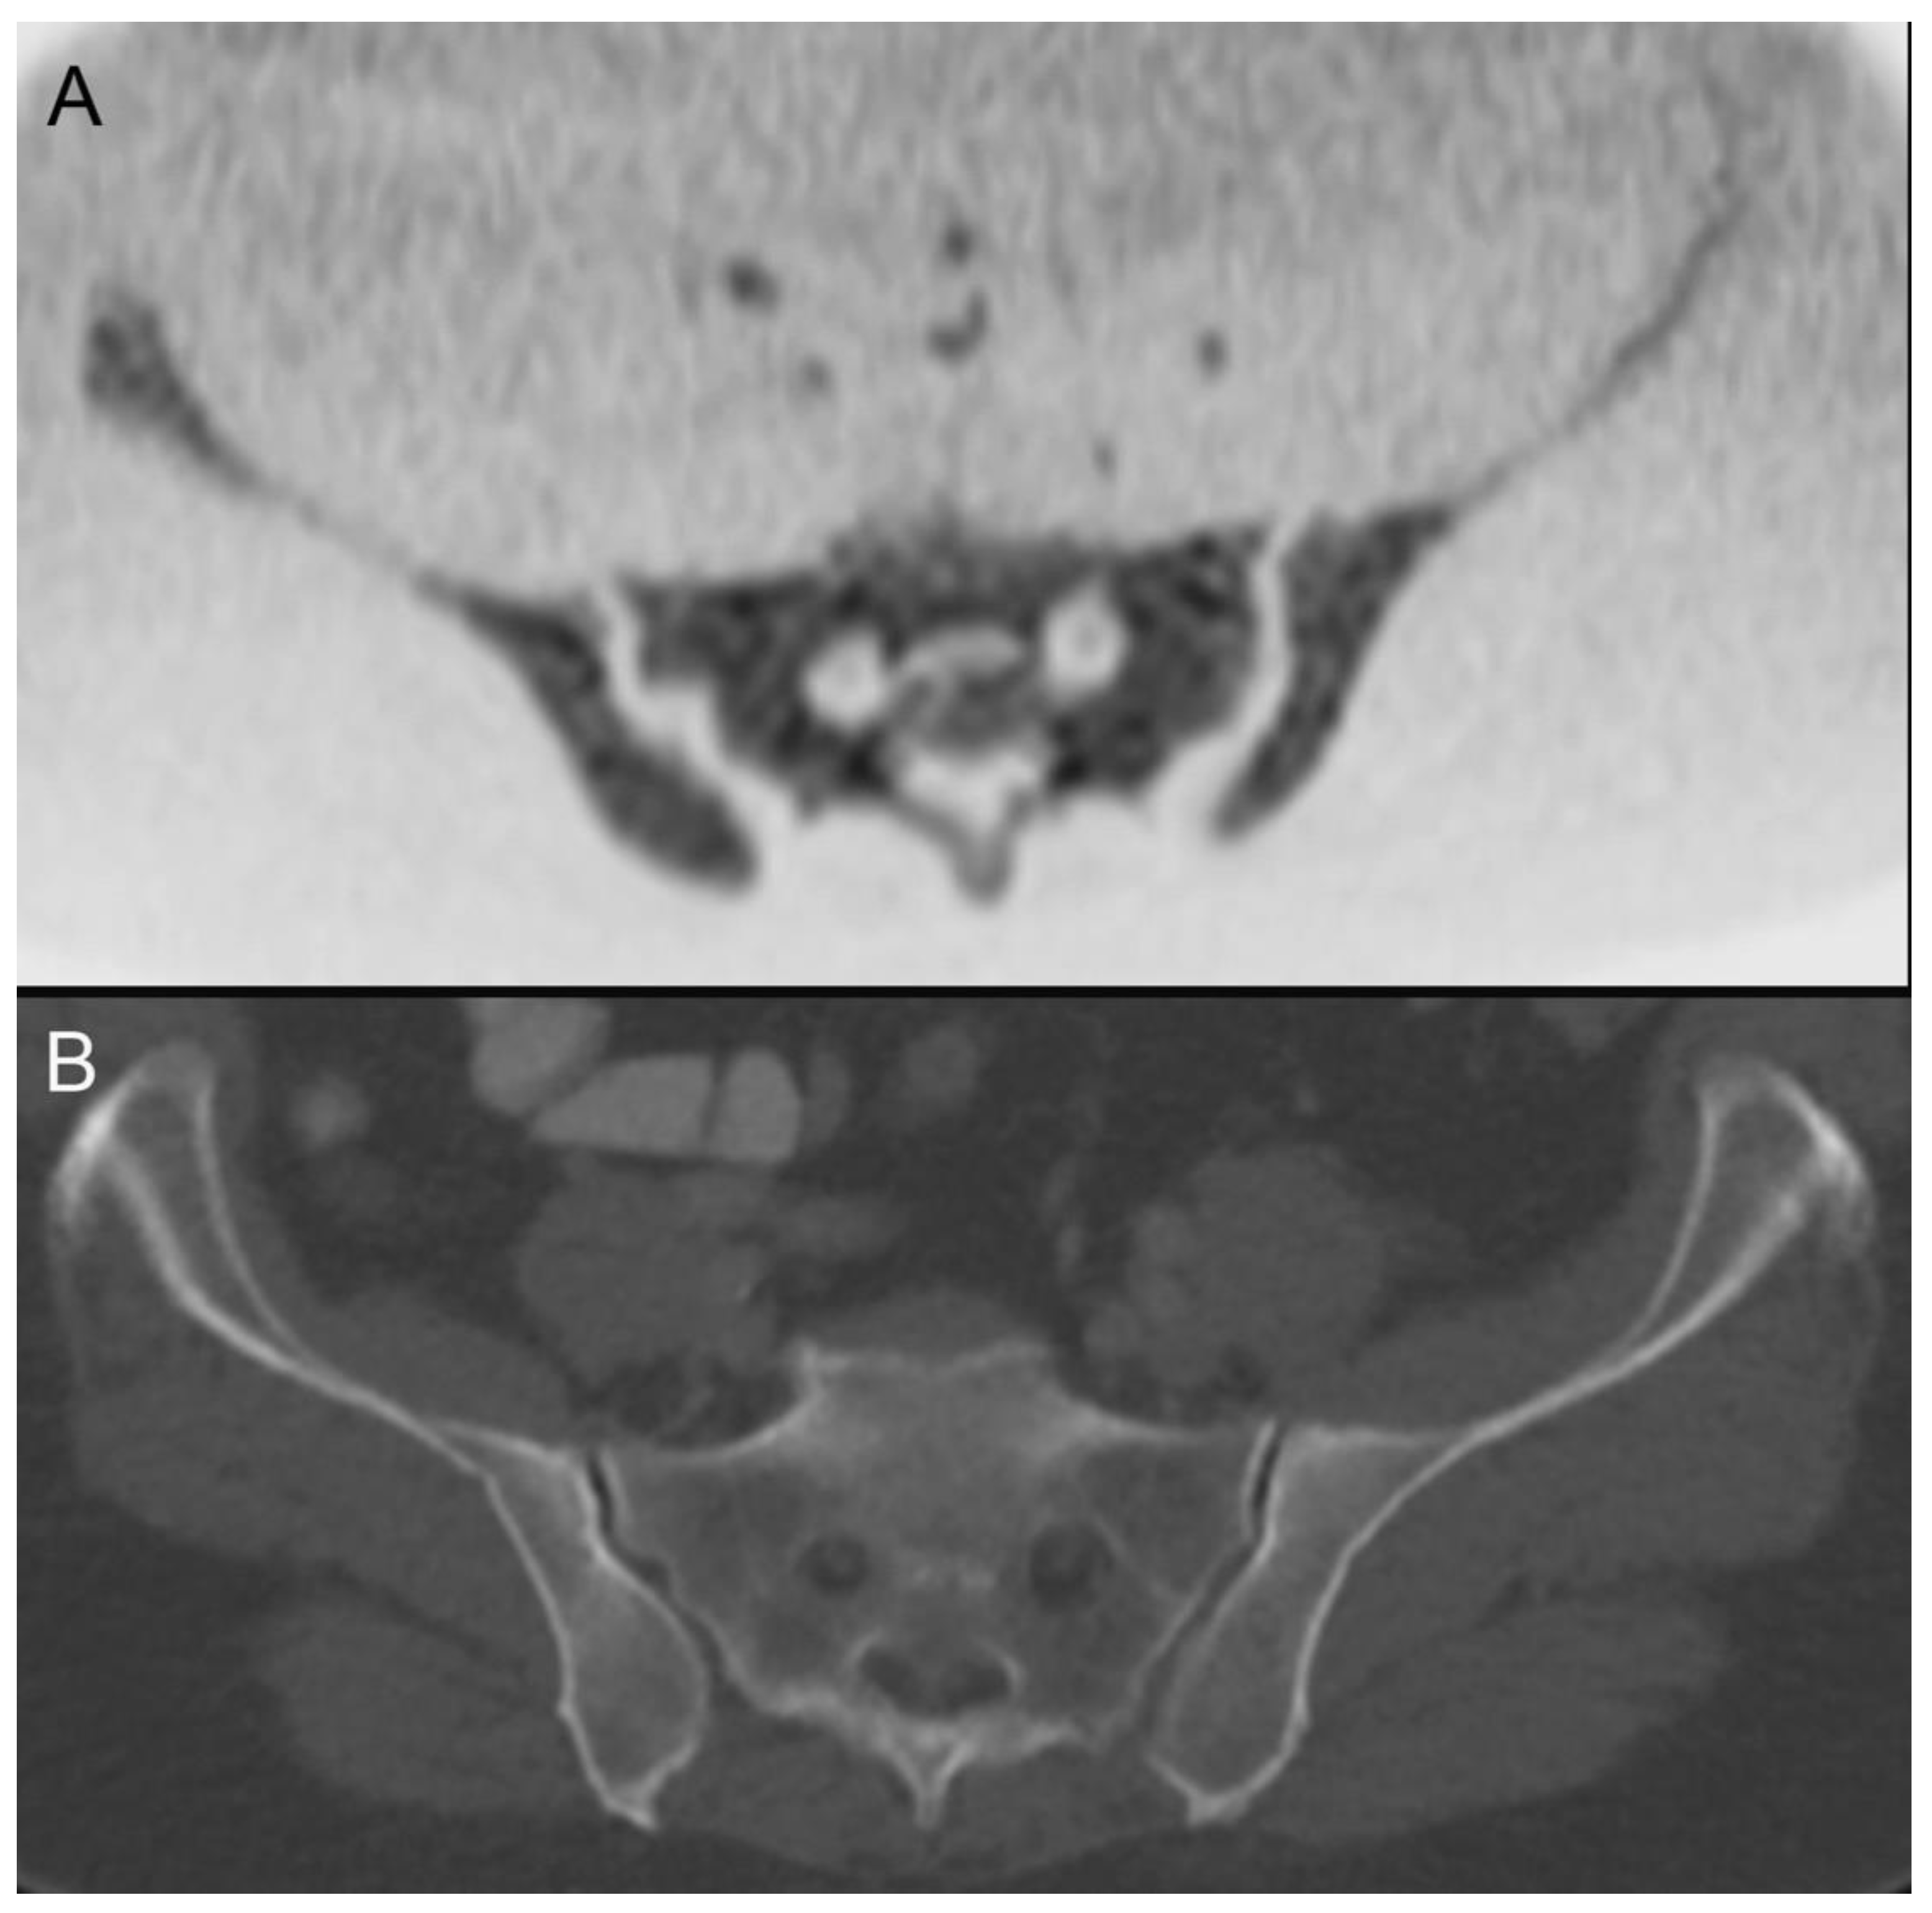

| 18 | leukemia (Figure 5) | ||